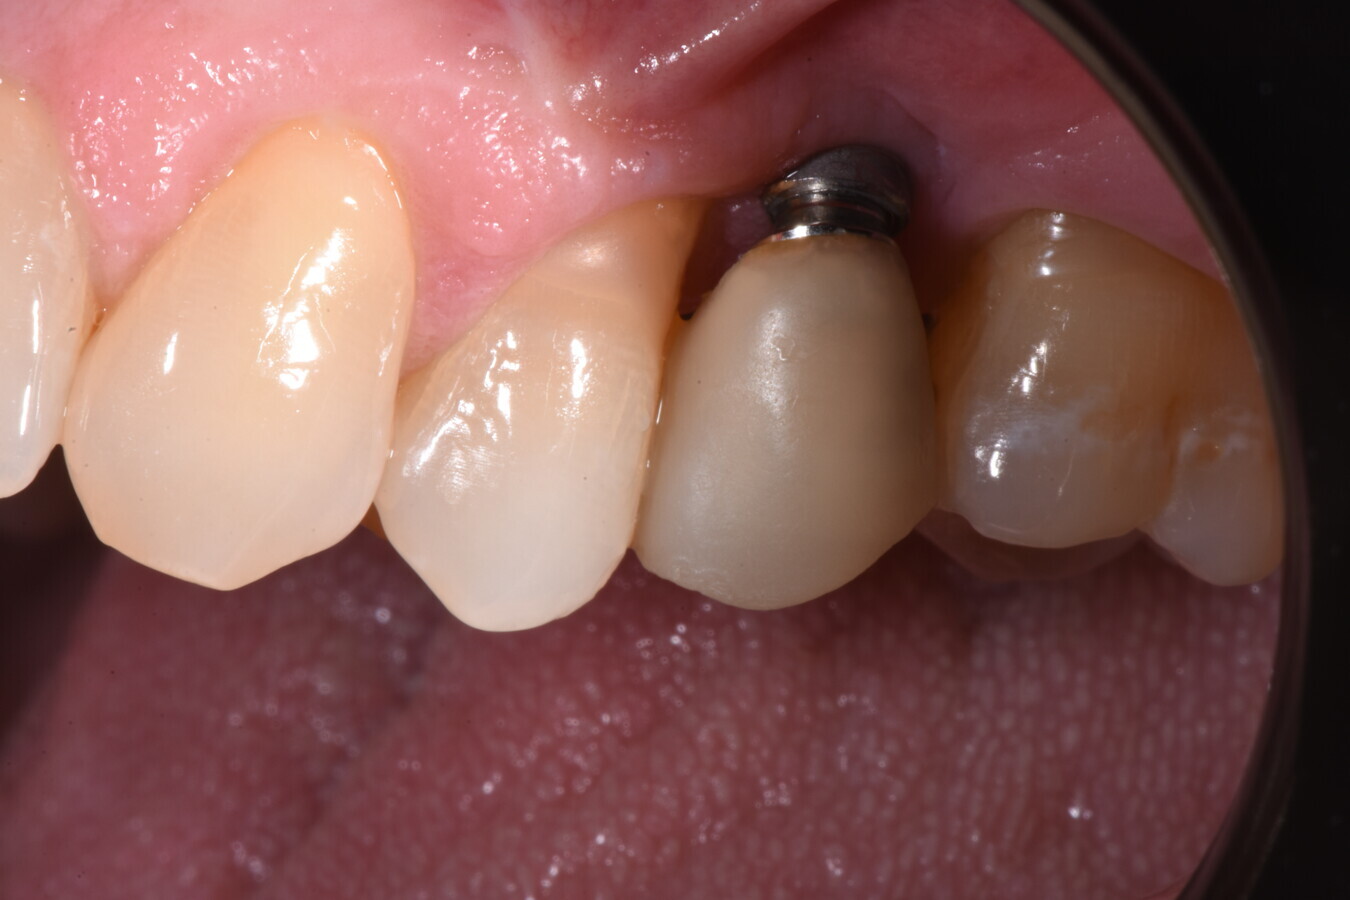

La paziente si presenta all’attenzione dello studio riferendo fastidi nella zona superiore sx, e all’anamnesi risultano trascorsi 3 anni dall’ultimo appuntamento di igiene presso altro centro. L’esame visivo e fotografico (Fig. 1) evidenziano un’alterazione dello stato dei tessuti perimplantari con sanguinamento spontaneo e lassità del tessuto molle, pertanto segue acquisizione di rx endorale da parte dell’odontoiatra (Fig. 2) da cui risulta un’importante riassorbimento osseo a carico dell’impianto. Segue un sondaggio perimplantare profondo (Fig 3), eseguito previa anestesia topica con Lidocaina 15%, per definire estensione e conformazione del difetto associandolo alla valutazione radiografica per la conta delle spire esposte.

Fig. 1

Fig. 2

Fig. 3

Si definisce un difetto con tipico aspetto a scodella, esteso a tutta l’area del perimpianto. Dalla sovrapposizione tra sondaggio ed esame radiografico, si evidenzia perdita del picco osseo distale all’elemento 14 indicando una prognosi peggiore dell’elemento implantare.